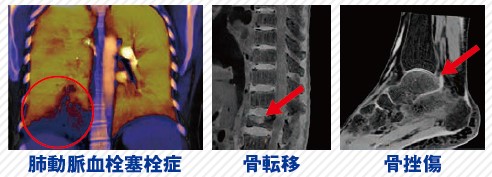

スペクトラル画像を使用した信頼性の高いCT検査 肺動脈血栓塞栓症や骨転移もCTで評価が可能!

1回のデータ収集で複数のスペクトラルイメージングを確認できるため、治療に関するより多くの情報を提供できます。